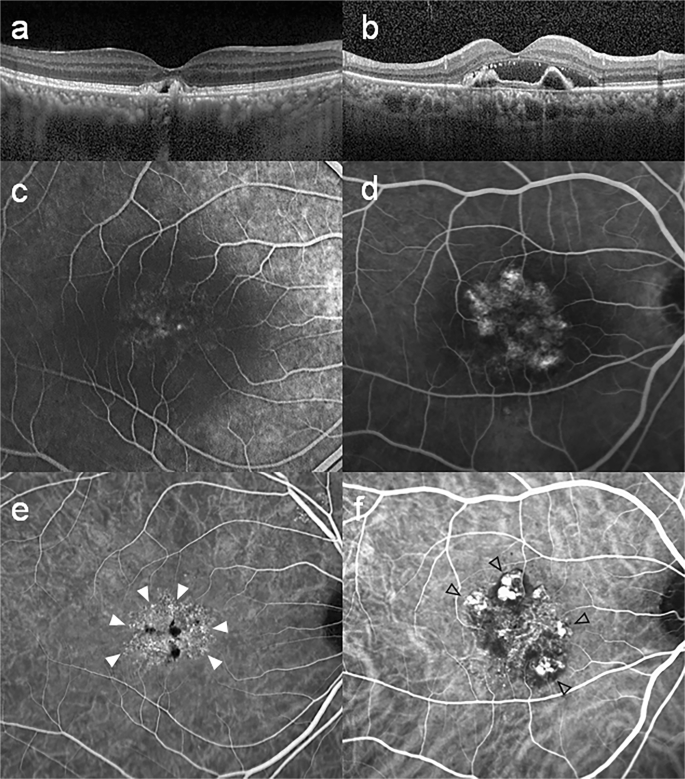

Sometimes there are ambiguous features on angiography, and retinal manifestations of PCV resemble those of chronic CSC or occult CNV12,19. Moreover, Uzawa et al.25 and Tan et al.26 advocated that the PCV is not a homogenous disease entity, but a spectrum of disease with discriminative characteristics. Previous study also revealed a lower anti-VEGF treatment response associated with thicker choroids in PCV patients27. These results are likely to be caused by the coexistence of different subtypes within the category we classify as PCV. In this regard, the refined classification system including MCV may reduce such debate and clarify the subtype of neovascular AMD. MCV is distinct from PCV by the absence of definite polyps. It is distinct from occult CNV by the presence of microaneurysms, which are connected with a lacy choroidal vasculature on ICGA (Fig. 3). The choroid of the MCV group patients was most thickened, and the baseline BCVA was the best among the subtypes. However, the MCV group only had one line of visual gain after 12 months of anti-VEGF treatment, which was inferior to that of the PCV group. These results suggest that the MCV group has its own characteristics that distinguish it from other groups.

Multimodal imaging of a 53-year-old male with microaneurysmal choroidal vasculopathy (MCV, left column) and 66-year-old male with polypoidal choroidal vasculopathy (PCV, right column). (a) Spectral domain optical coherence tomography (OCT) showing pigment epithelial elevation overlying a markedly thickened choroid and dilated choroidal vessels with minimal subretinal fluid. (b) Moderately thickened choroid is shown on OCT, and there is a discrete polypoidal structure between retinal pigment epithelium and Bruch’s membrane. (c,d) Early fluorescein angiography showing leakage from the choroidal neovascularization corresponding to the hyperfluorescent spots in indocyanine green angiography (ICGA). (e) ICGA in the early phase showing branching vascular network. Note that there is no definite polyp, other than small aneurysmal dilations (white arrow heads). (f) ICGA demonstrates multiple hyperfluorescent spots around the fovea corresponding to the polyps (opened black arrow heads) of PCV.